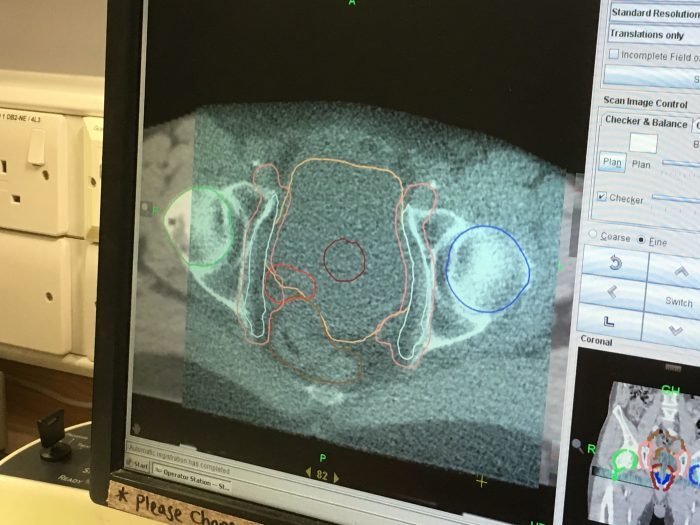

I’ve had 26 rides in the doughnut of doom and have a further 13 to complete the course. I asked Aaron, one of the radiographers, how many patients he treats in a day and he told me it’s between thirty and forty. That’s a lot of prostates getting clobbered by just one machine.